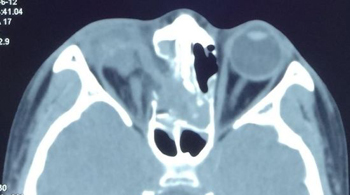

术后CT

术后患者依然存在眼部内陷及眶壁骨折,正在继续治疗中。